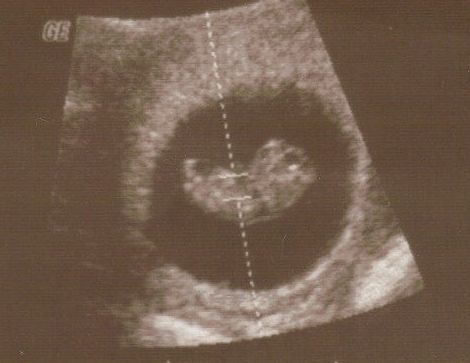

Oj widze ze dla moriam i joanna0984 dzieciaczki sie pleckami odwrucily ;-) Slodziaki!